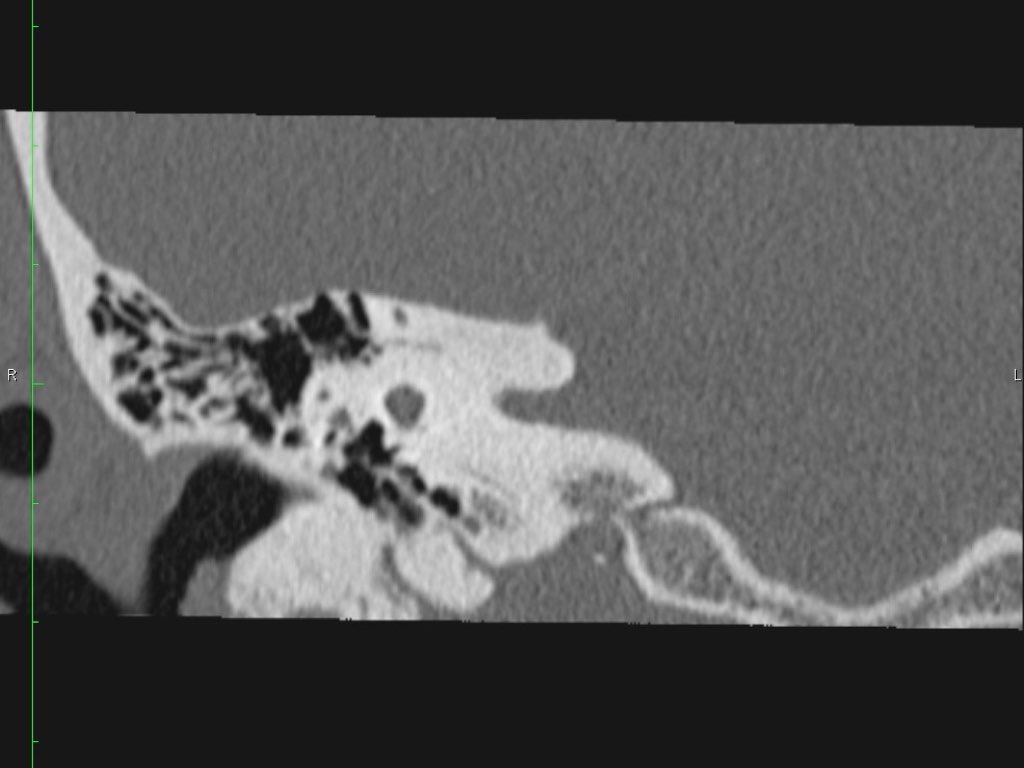

Hình ảnh một bệnh nhân có cholesteatoma.

Có một khối mô mềm ở vùng thượng nhĩ.

Lưu ý hình ảnh thủng màng nhĩ (mũi tên vàng) và bào mòn ống bán khuyên ngoài (mũi tên đỏ).

Scutum bị tù mòn.